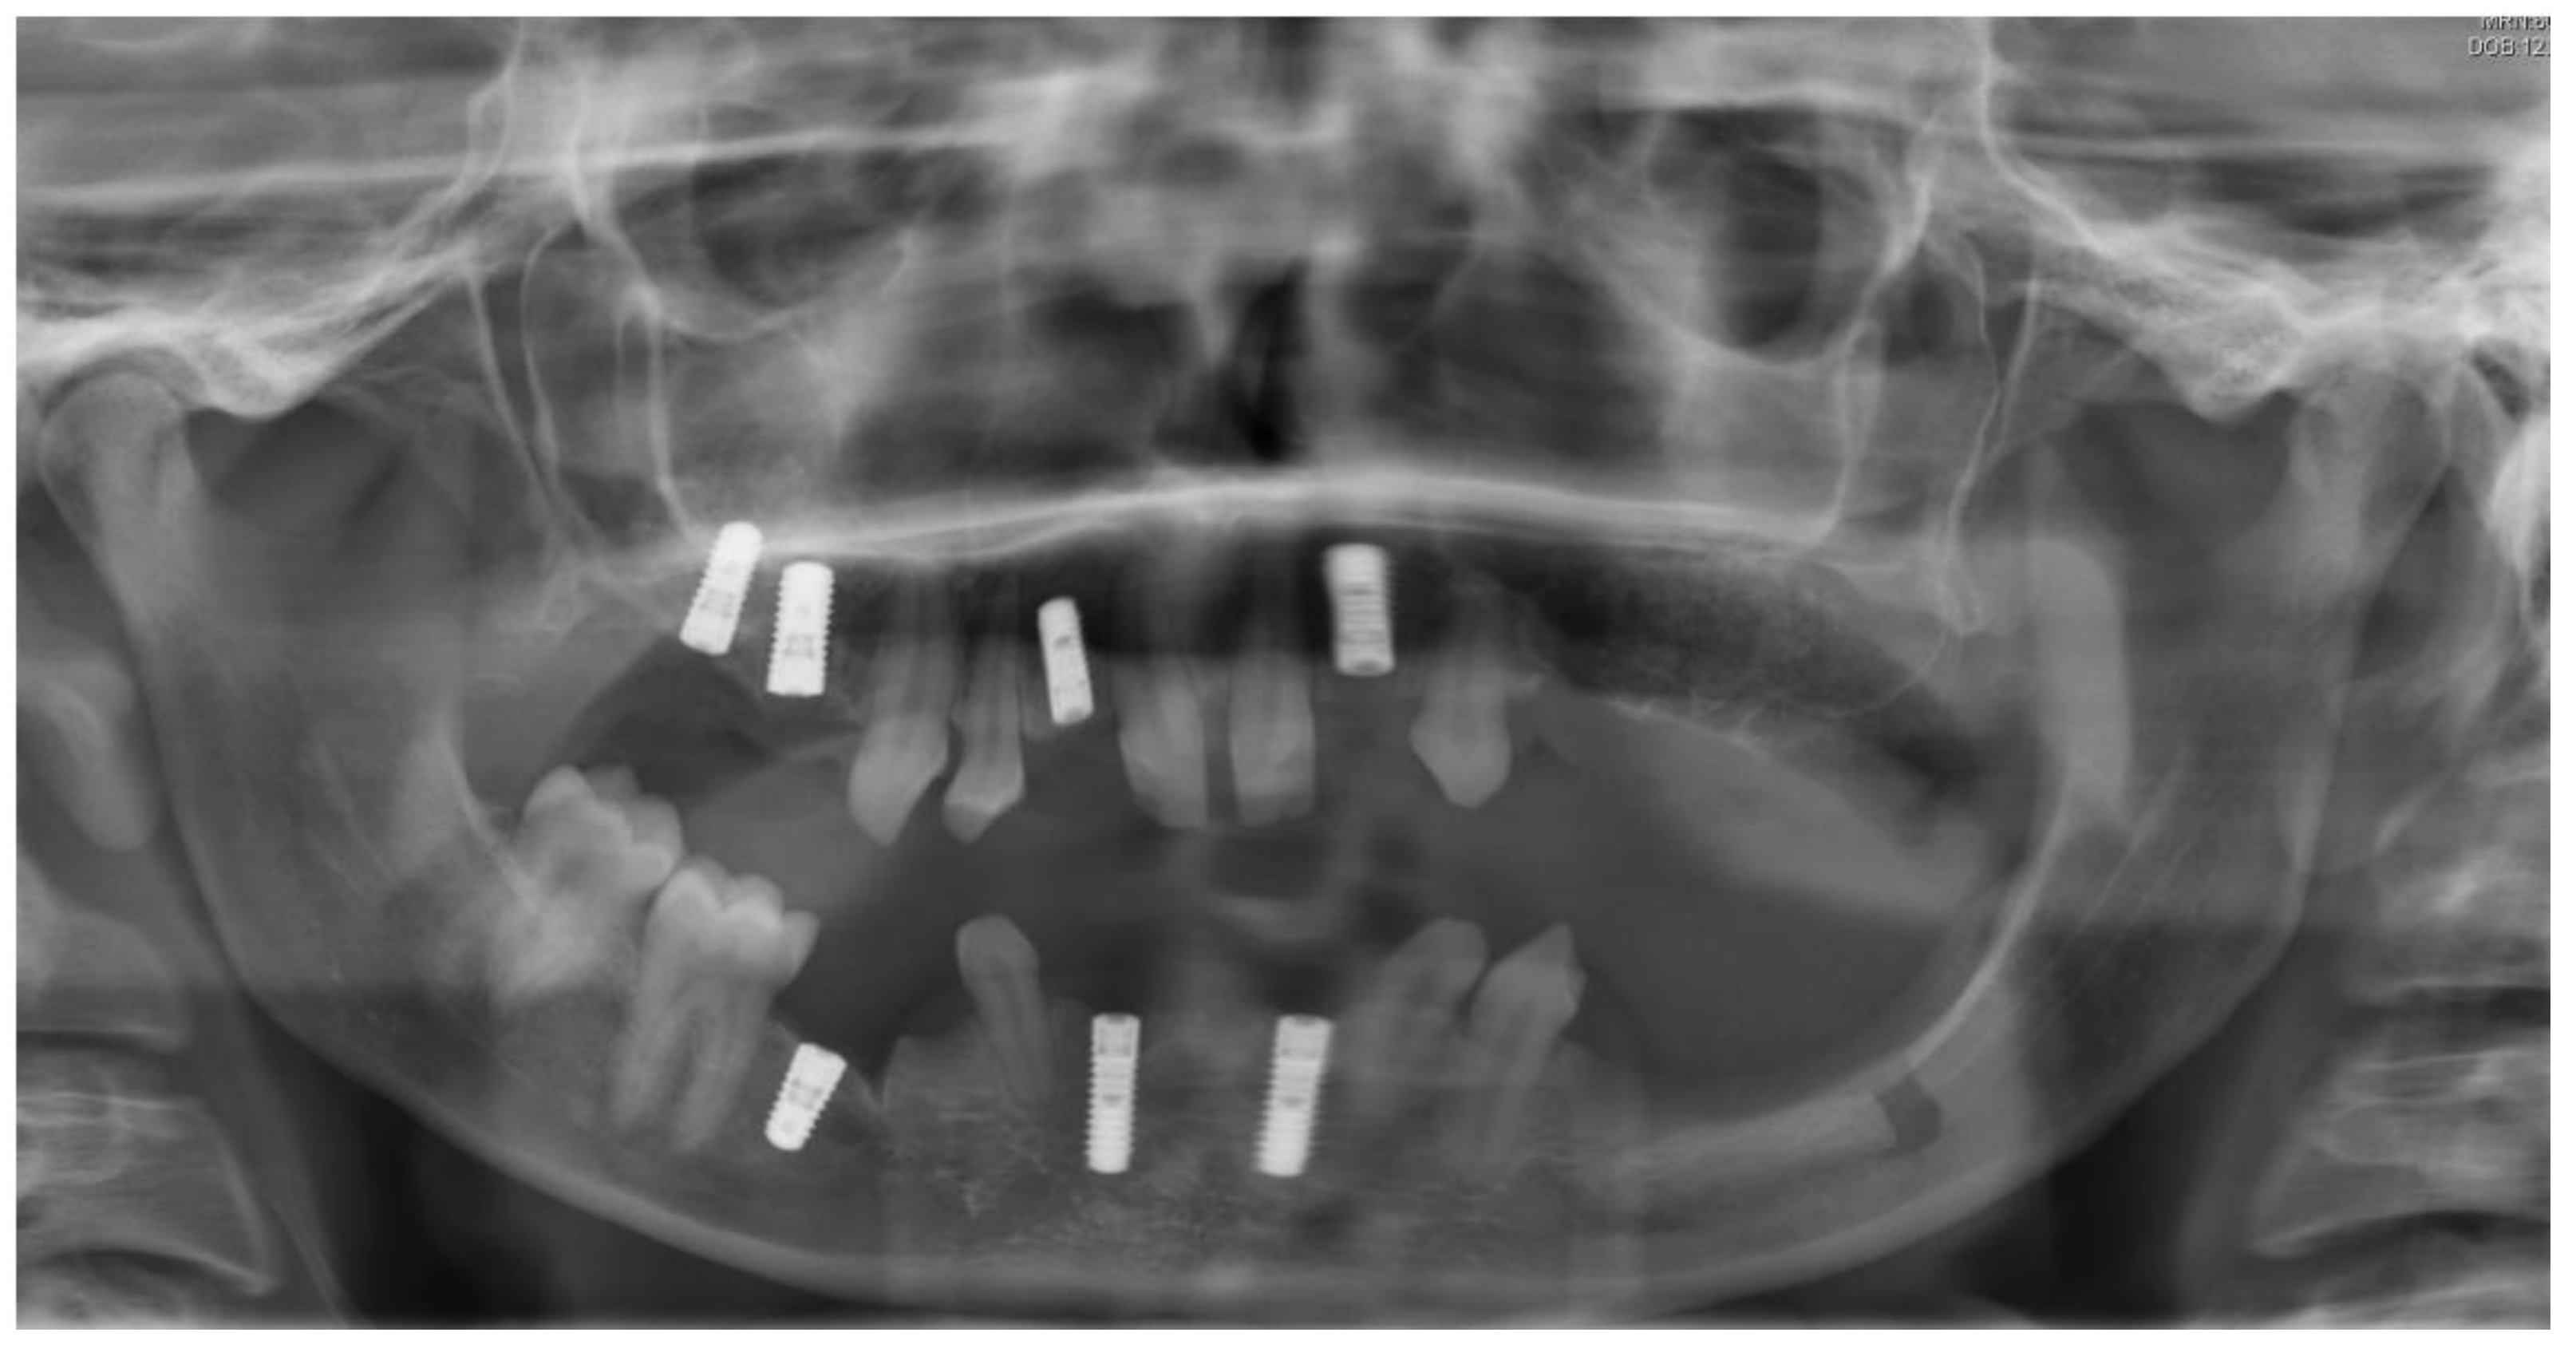

Figure 1.

Initial situation. Clinical examination showed absence of permanent teeth and persistence of primary dentition, abnormally shaped teeth, and unsatisfactory jaw relationship, suggesting the need of interdisciplinary treatment.

Figure 2.

Panoramic radiography after bone graft, nerve lateralization, and placement of dental implants in edentulous sites with adequate bone volume.

As soon as the orthodontic treatment was completed, the patient returned for dental implant planning. Regardless of adequate teeth alignment, the wide interproximal spaces, disproportional teeth dimensions, and abnormal occlusion increased the complexity of the case (Figure 1). Radiological examinations showed a reduced bone height at the edentulous site. In consideration of a bone atrophy in the upper and lower jaws, a two-stage surgical procedure was planned, which included bilateral sinus lift, nerve lateralization and placement of dental implants at the sites 16, 15, 12, 22, 35, 36, 32, 42, and 45 (Figure 2).